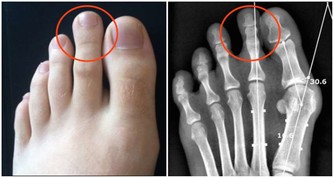

七、耳朵老是嗡嗡作響

這是腎功能在逐步衰退的信號,有時還會伴隨著腳痛、腰痛、尿頻等症狀,

工作過於勞累的人尤其要注意,要做到勞逸結合,

避免過度疲勞,少飲酒,少吃生薑、辣椒等刺激性強的食物。